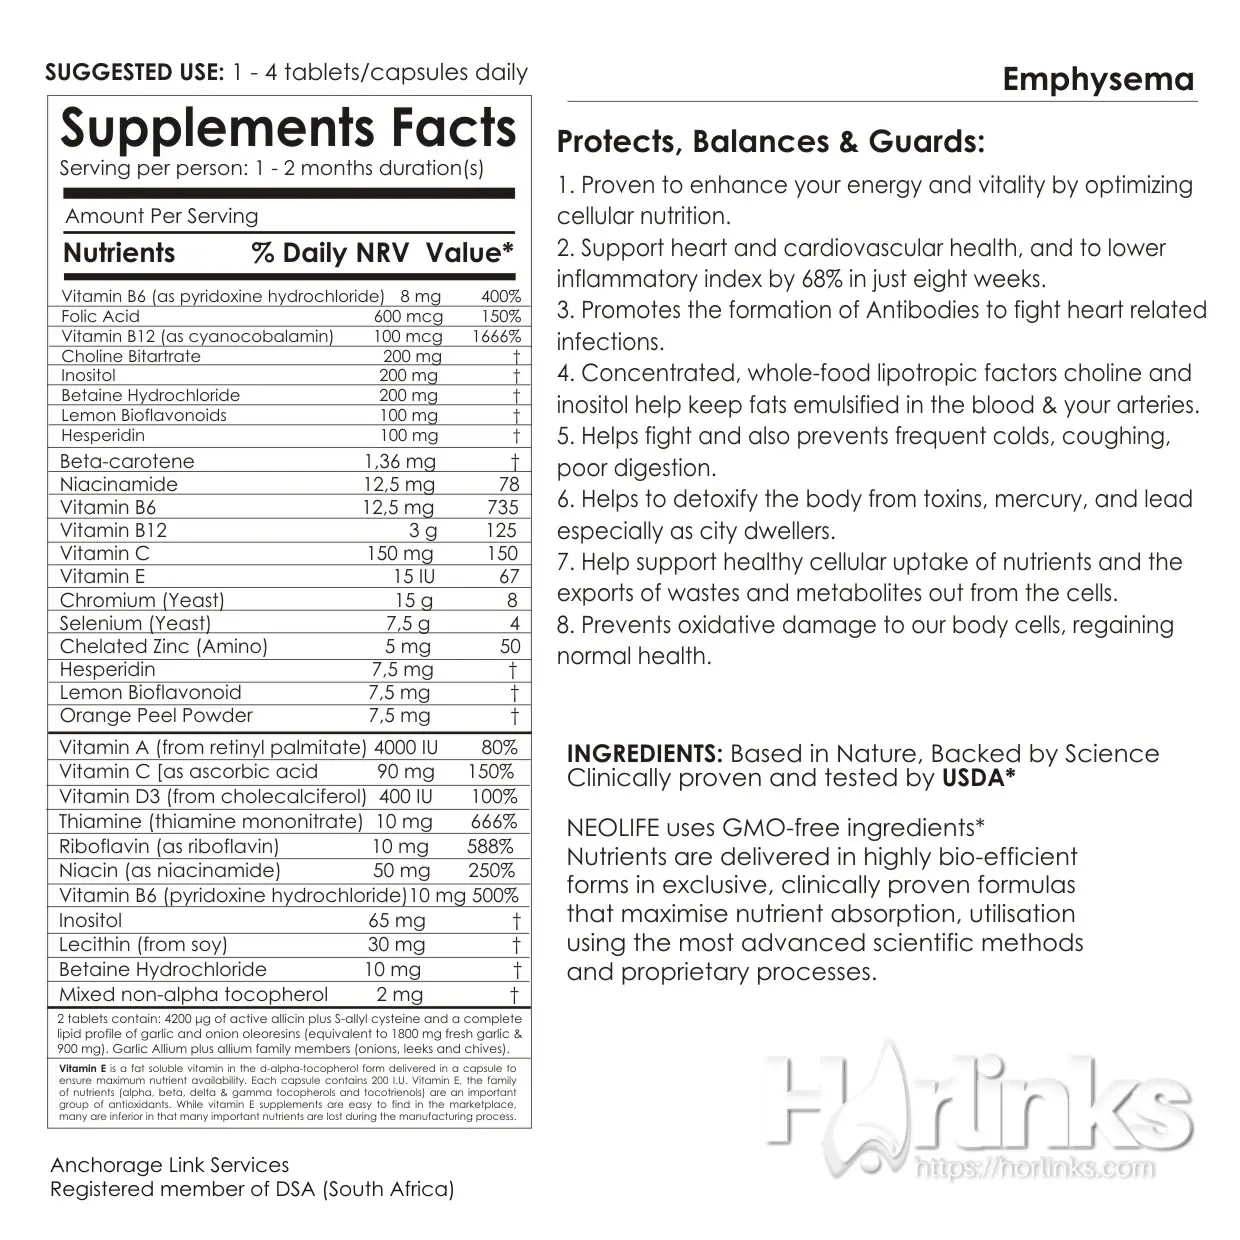

Quitting smoking is the most important way to protect your lungs, to help reduce inflammation in the airways. Doing this may relieve pressure on the breathing muscles and help improve lung elasticity (or stretch). Clinically, we recommend a conscious lifestyle and dietary changes immediately*! Also we urge you to take back your hearth health, helping your arteries metabolise promptly; with purification approach to re-balance your heartbeat functioning optimally with our Essential Nutritional Dietary Supplements by NEOLIFE;

1. Beta Guard in 100 Tablets; take 3 tablets daily.

2. Pro Vitality+ in 30 Sachets; take 1 sachet daily.

3. Vitamin C. Sustained Release in 100 Tablets; take 3 tablets daily.

4. Garlic Allium Complex in 60 Tablets; take 2 tablets daily.

5. Lipotropic Adjunct in 90 Tablets; take 3 tablets daily.

• Help support healthy cellular uptake of nutrients and the exports of wastes and metabolites out from the cells.

• Helps fight and prevent frequent colds, coughing, poor digestion.

• Helps to detoxify the body from toxins, mercury, and lead especially as city dwellers.

• Concentrated, whole-food lipotropic factors choline and inositol help keep fats emulsified in the blood and your arteries.

• With B6, B12 and folic acid help lower homocysteine levels, found responsible for approximately 18% of all heart attacks and stroke worldwide today.

• Citrus bio-flavonoids support the health of blood vessels, important for carrying lipids throughout the entire body tissues*!

• Promotes the formation of Antibodies to fight heart related infections.

Each packet of Pro Vitality provides daily whole food nutrition for lifelong health and vitality from whole grains, fruits & vegetables, fish and vitamins & minerals*!

Powerful nutrients that support: Abundant Energy, Powerful Antioxidant Protection, Lifelong Heart Health, Optimum Immune Strength, Healthy Brain Function, Flexible, Healthy Joints, Clear Vision, Youthful Skin, Hair and Nails, Lifelong Cellular Health and Natural Genetic Anti-Aging Function

Based in Nature, Backed by science!

The Right Supportive Formulas by Food and Nutrition Board, Institutes of Medicine Dietary Reference! The Scientific Advisory Board (SAB) seal guarantees you the finest, safest, most effective products in the world. Ensuring your body gets the BESTS of maintenance with NEOLIFE’s rich Vitamins & Minerals!

Clinically Tested and Proven Nutritional Whole-food Supplements from mother-nature.